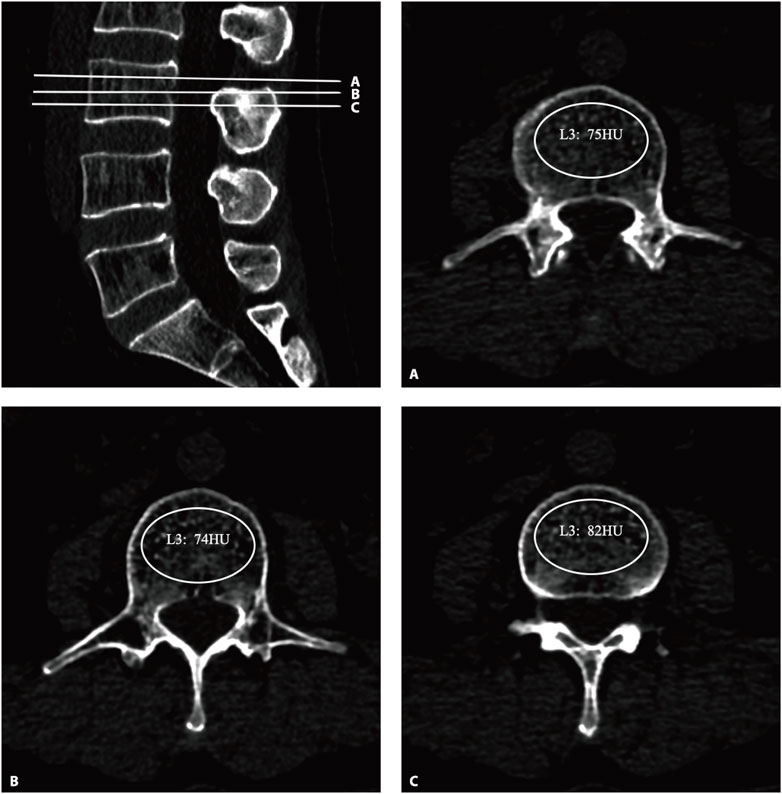

All the subjects underwent three-dimensional (3D) lumbar CT (GE Optima CT660−ΔΔCT, United States), The parameters were as follows: tube voltage 120 kV; collimation, 64 × 0.625 mm; field of view (FOV), 500 mm; The CT scan data were transferred to the workstation and reconstructed with standard algorithms with reconstruction layer thicknesses of 1.25 mm, displaying a field of view of 380 mm; reconstruction matrix: 512 × 512. After the 3D CT image was reconstructed, the upper, middle, and lower planes of each vertebral body were selected to establish an elliptical region of interest (ROI) on the upper, middle, and lower planes perpendicular to the vertebral axis. The ROI was selected to include as much trabecular bone as possible and to exclude cortical bone, the posterior venous plexus, and bone islands (Figure 1). The mean of the HU values of the three ROIs for each vertebral body was recorded as the HU value of the vertebral body, and the mean of the HU values of L1–5 was calculated as the total spine HU value for this patient. According to previous studies, the diagnostic threshold of OP with high sensitivity and specificity was determined to be 110 HUs (Alawi et al., 2021; Xue et al., 2024; Zou et al., 2019; Pickhardt et al., 2013; Wagner et al., 2016).

Figure 1. The HU values were derived from CT. An oval region of interest is positioned on the axial plane of the vertebrae (A–C), with the HU value being automatically calculated by the image archiving and communication system. HU, Hounsfield unit.